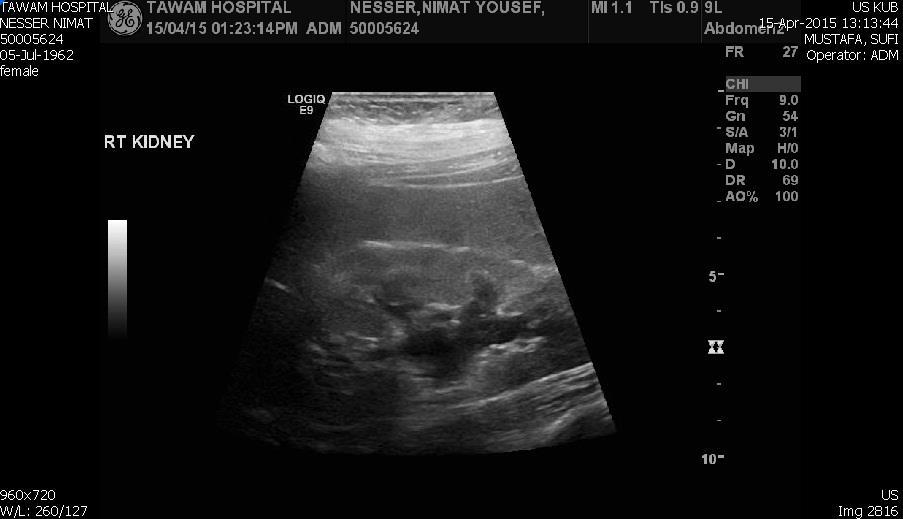

Blood tests on April 14th showed: Na = 131, K = 5.1, Urea = 6.9, S. Creatinine = 96, and eGFR = 61ml/min. Urine analysis and cultures confirmed E. coli urosepsis, blood cultures were negative. Renal US revealed echogenic kidneys, mild bilateral hydronephrosis of about 12 mm with normal ureters and urinary bladder (Figure 1 and Figure 2). Treatment with oral antibiotics resulted in improvement of temperature and dysuria. On April 20th patient seen by endocrinology and nephrology because of persistent back pain, dapagliflozin was discontinued and followed by resolution of symptoms in few days. Patient had two kidney ultrasounds in May and June, both indicated gradual resolution of bilateral hydronephrosis. Repeat CT of the abdomen on July 7th revealed complete resolution of hydronephrosis (Figure 3). Most recent eGFR is 72 ml/min.

Figure 3.CT Scan showing bilateral kidneys with no hydronephrosis

CT Scan showing bilateral kidneys with no hydronephrosis